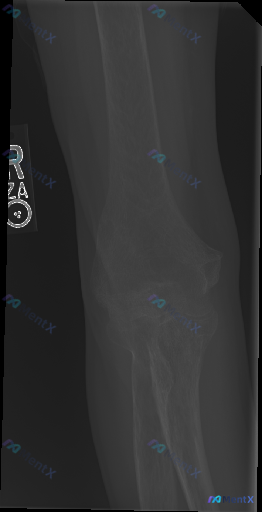

整理到一张右侧肘关节正位X光的读片讨论:

- 肱骨远端、尺桡骨近端骨质连续,关节对应关系尚可

- 关节间隙无明显狭窄/增宽,软组织也没看到明显弥漫肿胀

- 报告写的是「未见明显急性骨折或关节脱位征象」

但有意思的是,这份资料明确标注了「存在异常(Abnormality present)」。